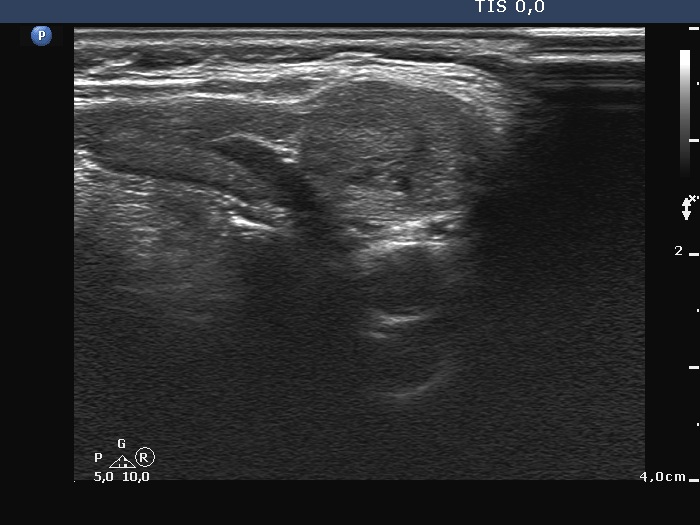

Ultrasonography. There was no thyroid tissue in the thyroid beds. Approximately 7 cm above the thyroid in the left side of the neck there were multiple, moderately hypoechoic lesions which presented tiny cystic areas. They had vascularity but did not have capsule.